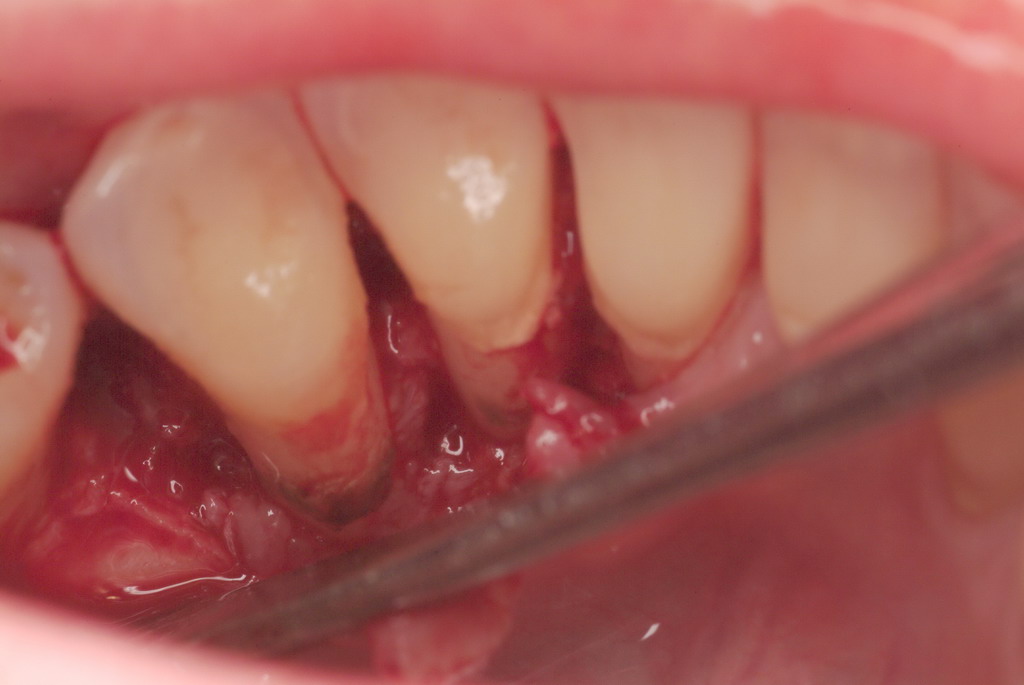

In a case with an intrabony defect, such as with the patient in Figure 17, a periodontist might suggest sacrificing supporting bone to remove the osseous defect. Doing this might lead to issues related to tooth mobility, esthetics, caries, and hypersensitivity.

The patient had been referred for an implant consultation for the mandibular right canine. She had very deep probing depths on the lingual. When the flap was raised, a significant amount of subgingival calculus was seen as a local risk factor (Figure 18). However, she had no significant pathology to remove from the situation. Debridement was performed the same as in Case 3 with the rotary ultrasonic and manual instrumentation.

Subgingival calculus and severe bone loss.

Figure 18